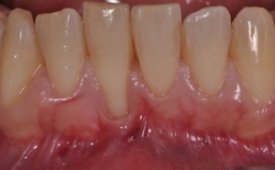

Se le realizó tratamiento desinflamatorio de toda la boca, apreciándose una gran mejoría (Foto 2) aunque la paciente refería dificultades para mantener la zona en adecuadas condiciones higiénicas.

Foto 2